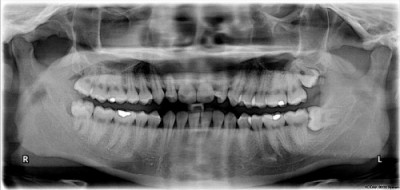

Stoma

Zilele trecute am făcut o operaţie: rezecţie apicală la un dinte pluriradicular. Nu mă durea nimic iniţial, ci doar am observat o mică umflătură pe gingie, deasupra unei măsele. Mi-am făcut o radiografie panoramică (precedată bineînţeles de un test de sarcină negativ) pe care au interpretat-o atât medicul stomatolog cât şi cel de la chirurgie maxilo-facială. Aveam două variante: extracţie - 50 lei - sau operaţie - 400 lei -  pentru a putea păstra dintele. 400 lei e o sumă importantă pentru bugetul familiei, aşa că m-am interesat cam cât aş putea beneficia de rezultatele metodei conservatoare. Stomatologul m-a asigurat că 10-15 ani după operaţie tot ţine măseaua cu pricina. Am hotărât deci să optez pentru varianta mai scumpă. Am aflat apoi că înainte de intervenţie trebuie să am canalele obturate la dintele respectiv, dar această manevră trebuie făcută cu puţin timp înainte, de preferat chiar în aceeaşi zi, altfel risc să apară dureri insuportabile. Dimineaţa am fost la dentist, iar la ora 16 aveam programare la cabinetul chirurgului.

Din fericire am fost prima pe listă în ziua respectivă, altfel aş fi avut mult de aşteptat (programările sunt făcute la intervale de timp nerealiste după cum am aflat ulterior de la alţi pacienţi). Medicul a fost foarte atent să nu doară nimic. Nu ştiu dacă asta s-a datorat sensibilităţii lui sau aşa fusese instruit, dar am fost încântată că anestezicele şi-au îndeplinit rolul. Imediat după incizie a drenat o colecţie purulentă abundentă, apoi a urmat rezecţia rădăcinilor şi chiuretajul zonei de maxilar afectate. Canalul bolnav era cel palatinal, iar infecţia ajunsese până la sinusul maxilar drept. Au avut de lucru cam o jumătate de oră pentru a curăţa totul. Au incizat maxilarul şi pe exterior şi prin cerul gurii şi am avut nevoie de 4-5 fire. La sfârşit am primit o reţetă cu un antibiotic (Cuminol), un antiinflamator (Diclotard), ceva pentru a-mi proteja mucoasa gastrică (Omeran) şi ceva împotriva durerii (Algifen). Toate erau prescrise 7 zile. Alăptez încă, aşa că iau doar antibioticul, deşi pe prospect scria că se elimină şi prin lapte. Grigo n-a avut nici o reacţie macroscopică la laptele cu antibiotic.

Acasă, a doua zi după operaţie, mi s-a umflat obrazul şi ochiul drept, dar am aplicat comprese cu apă rece şi s-a mai diminuat edemul. Durerile au fost suportabile, dureri surde care n-au avut nimic în comun cu durerile ascuţite de dinţi de care mă temeam. Am avut voie să mănânc după două ore alimente moi, să mă clătesc cu ceai de muşeţel şi să mă spăl în mod obişnuit pe dinţi. Mi s-a spus să mă feresc de curent şi vânt, de alimente şi băuturi fierbinţi, să nu mestec nimic pe partea respectivă timp de o săptămână. La control am fost chemată după două zile, iar la scoaterea firelor după 7 zile.

Ca o completare la postarea de aici ţin să menţionez că am făcu o complicaţie la operaţia respectivă : sinuzita odontogenă. E destul de frecventă, nu ştiu dacă se datorează unui act medical neglijent sau doar faptului că "a pătruns mâncare" aşa cum mi s-a explicat cu ridicări de umeri de către medici. Eu ştiu că m-am îngrijit să direcţionez solidele doar pe partea sănătoasă dar nu pot demonstra asta, pentru că "nu avem cameră de luat vederi în gură". De asemenea nu mi-am suflat deloc nasul post-operator, manevră care poate duce la desprinderea suturii. Cert este că am rămas cu o comunicare alveolo-sinusală (între locul de implantare a dintelui şi sinus şi, prin urmare, nas) şi cu sinusul drept plin cu puroi.

În prezent fac puncţii sinusale la un cabinet ORL (consultaţia 40 lei, fiecare puncţie 30 lei) şi am fost avertizată că voi face o a doua intervenţie maxilo-facială între două reprize de câte 5 puncţii sinusale. Puncţia în sine nu e dureroasă. E traumatizantă mai mult psihic(senzaţia de penetrare a osului cu acul de puncţie are o încărcătură aparte pentru mine). Singurul lucru care doare e anestezia. Sânge curge foarte puţin, câteva picături.

Dacă nu reuşeşte nici de data asta sutura va trebui să fac operaţie în secţia ORL pentru a închide sinusul. Momentan şansele de a evita operaţia sunt cam de 40 % . O fericire!